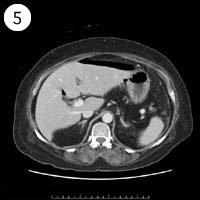

57歳 女性

単純CT

造影CT